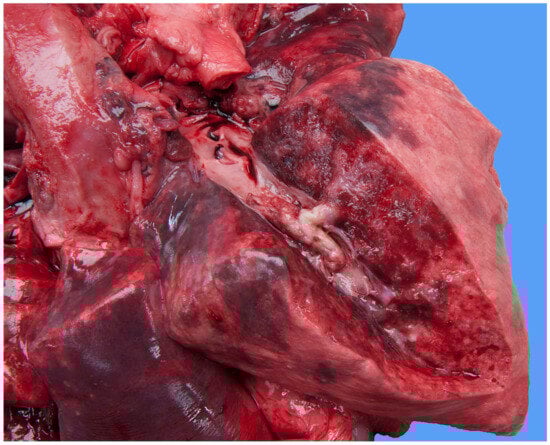

Focally extending throughout the right ventricular lumen and partially incorporating the chordae tendineae and tricuspid valve leaflets, was a large (6 × 4 × 4 cm) thrombus adhered to the endocardium. A length of approximately 3 cm of the pacing electrode was embedded within the thrombus (Figure 7). The myocardium of the adjacent interventricular septum and free ventricular wall showed patchy white discoloration. The site of the tip of the electrode was visible in the apex as a small, slightly indented, firm, white area of connective tissue. Thrombus material filled the lumens of the right and left pulmonary arteries (Figure 8). The lungs were mildly congested and edematous. There was moderate congestion in the liver and mild ascites.

Figure 7.

Necropsy shows the right side of the heart and mediastinum of the dog. The walls of the jugular vein, the right atrium and the right ventricle are open allowing the visualization of the lumen. The pacemaker lead disappears in the pale soft tissue mass that fills the right ventricular chamber.

Figure 8.

Necropsy shows a large thrombus in the pulmonary artery of the right caudal lung lobe of the dog. The lung parenchyma has an edematous aspect.